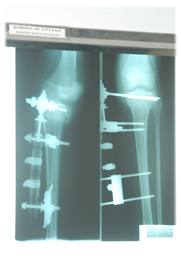

"เครื่องมือยึดจับกระดูกจากภายนอกชนิดยืดหยุ่น" คือกลไกที่ นายแพทย์อนุชิต คิดขึ้นมาเพื่อใช้รักษาภาวะกระดูกหัก โดยเฉพาะบริเวณหน้าแข้ง ซึ่งมีราคาถูก ใช้งานง่าย ผู้ป่วยพึงพอใจ รวมทั้งได้รับรางวัลจากสถาบันต่างๆ อย่างน่าภาคภูมิใจ

เจ้าเครื่องมือยึดจับกระดูกจากภายนอกชนิดยืดหยุ่นนี้ คือการเปิดมิติใหม่ของการผ่าตัดใส่เหล็กเพื่อรักษาอาการ "กระดูกหัก" แบบเดิมๆ แล้วเปลี่ยนมาใช้เครื่องมือชนิดใหม่เพื่อช่วยยึดจับกระดูกจากภายนอก แถมยังใช้วัสดุที่มีสีสันสดใสสบายตา ทำให้ผู้ป่วยสบายใจ

น.พ.อนุชิต เล่าถึงการสร้างสรรค์นวัตกรรมอันน่าทึ่งนี้ว่า เมื่อเกิดอุบัติเหตุ เช่น รถชน แล้วกระดูกหน้าแข้งหัก การผ่าตัดแบบเดิมคือการผ่าตัดเปิดแผลแล้วใส่เหล็กดามเข้าไป ซึ่งการผ่าตัดแบบนั้นเป็นการไปทำลายเนื้อเยื่อที่ดีอยู่ให้เป็นเนื้อเยื่อที่ถูกทำให้บาดเจ็บ ทั้งๆ ที่โดยธรรมชาติกระดูกที่หักจะต่อติดกันได้ด้วยเนื้อเยื่อรอบข้างที่ดี แต่เรากลับไปทำลายเนื้อเยื่อที่ว่านั้น

นายแพทย์อนุชิต เล่าต่อว่า สำหรับการผ่าตัดที่ใช้เครื่องมือชนิดใหม่ที่เขาคิดค้นขึ้นนั้น เป็นการผ่าตัดครั้งเดียวเพื่อนำเครื่องมือทาบลงไป ก็เสร็จเรียบร้อย

"เครื่องมือนี้ทำให้ไม่ต้องผ่ามาก เพราะกระดูกคนเราถ้าเอามาต่อกัน เนื้อเยื่อจะสมานกันได้เร็วมาก แผลก็หายเร็ว เราใส่เครื่องมืดเข้าไปเพื่อยึดให้กระดูกติดกันใช้เวลาประมาณ 1-3 เดือน เครื่องมือมีความยืดหยุ่น สามารถดึงเข้าดึงออก ปรับหมุนซ้ายขวาได้ เราออกแบบให้ปรับเปลี่ยนได้ น้ำหนักเบา สวยงาม ราคาถูกมาก ตัวเดียวจบ ประหยัดงบประมาณไปได้เยอะ ถ้าเป็นเมืองนอกราคาเป็นแสน บางตัวอาจถึง 5 แสนบาท แต่ปรับได้แค่เข้า-ออก แต่ของเราหมุนซ้าย-ขวาได้ด้วย"

บรรยายภาพ :

2-4 ฟิล์มเอ็กซเรย์ กับ เครื่องมือยึดจับกระดูกจากภายนอกชนิดยืดหยุ่น